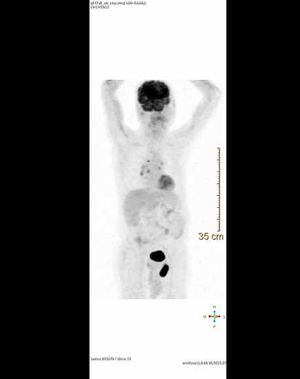

Case History: 45-year-old with history of brain tumor with complaints of abdominal pain.